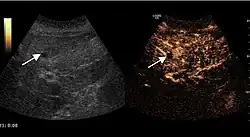

Liver abscess (2D and CEUS). 2D Examination reveals the fluid nature of the mass and imprecise delineation. CEUS examination shows congestion in the surrounding liver parenchyma and excludes a vascular tumor.

Liver abscess have heteromorphic ultrasound appearance, the most typical being that of a mass with irregular shapes, fringed, with fluid or semifluid content, with or without air inside. Doppler examination shows the lack of vessels within the lesion. CEUS exploration shows hyperenhancement during arterial phase close to the lesion, this being suggestive of a liver parenchymal hyperemia. During venous and sinusoidal phase the pattern is hypoechoic, and the central fluid is contrast enhanced. CEUS examination is useful because it confirms the clinical suspicion of abscess. In addition, it allows for an accurate measurement of the collection size and an indication regarding its topography inside the liver (lobe, segment).